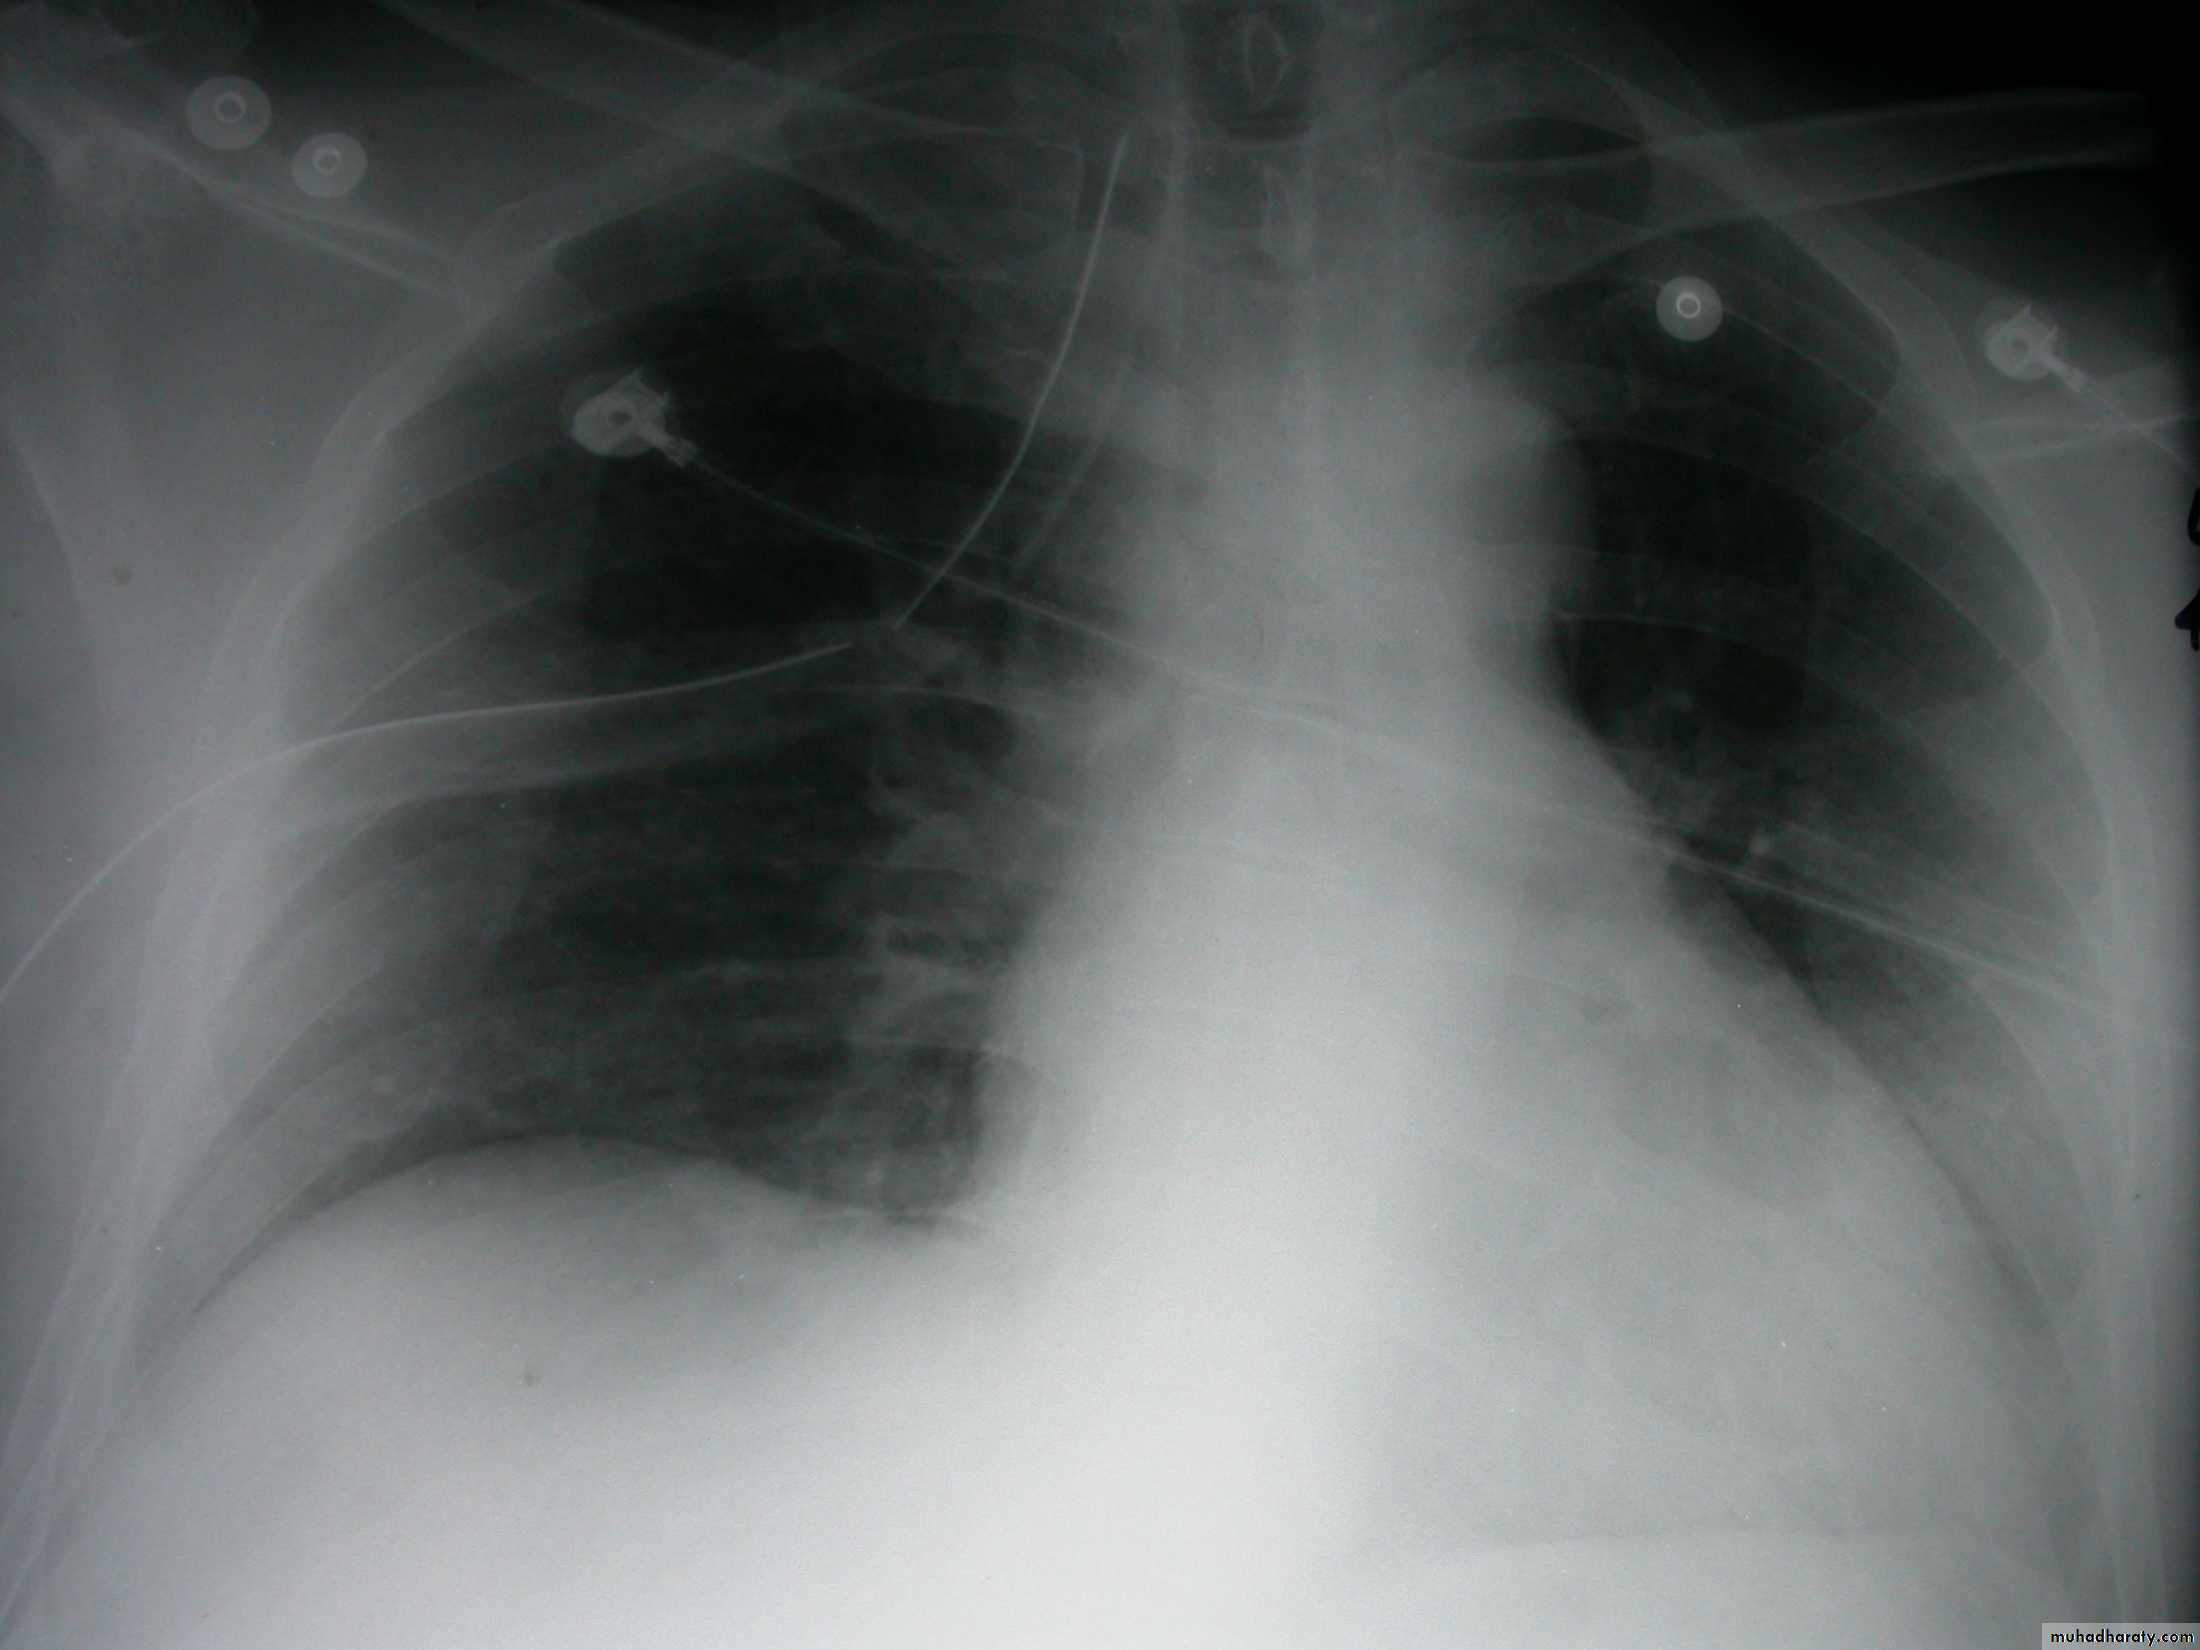

Fall from the 2nd floor